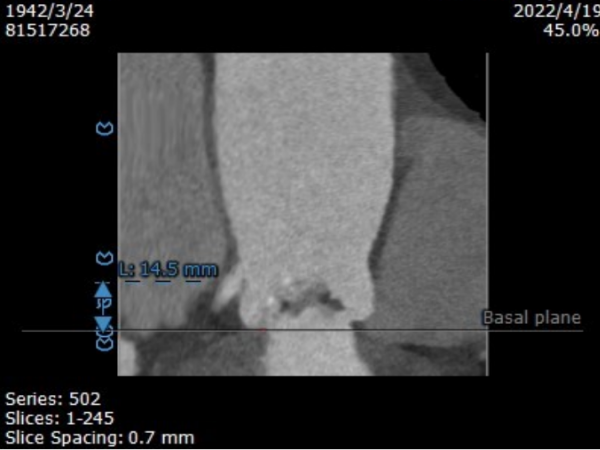

左冠开口高度14.5mm,右冠开口高度12.1mm,双侧冠脉开口未见明显附壁钙化,结合瓦氏窦宽度和瓣叶长度综合判断冠脉阻挡风险低。